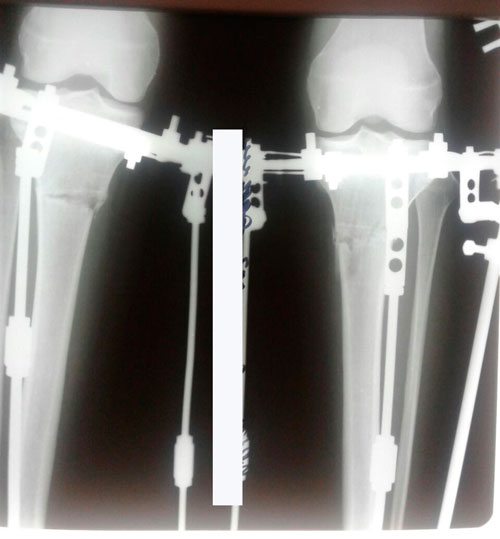

хотела поделиться своими новостями, сегодня 67-й день с аппаратами илизирова, по прогнозам Н Николаевича аппараты снимут в начале апреля

. Очень жду этого дня) хотя к аппаратам уже давно привыкла и не жалуюсь на боли и дискомфорт.

Дата операции 17.01.2018г.

Дата снятия аппаратов 21.05.2018г.

Срок лечения 123 дня.